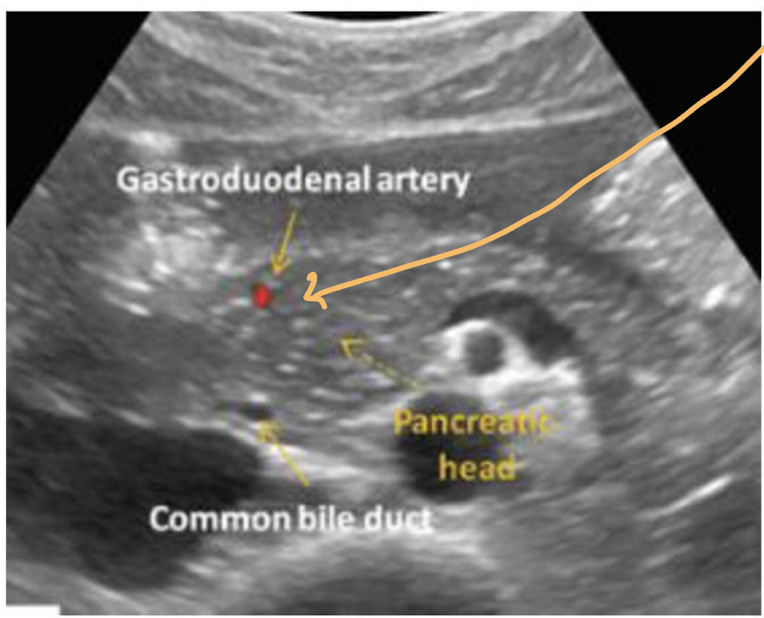

Which round anechoic structures can be visualized within the pancreatic head

Gastroduodenal artery (GDA) & Common Bile Duct (CBD)

Usually within the pancreatic head the gastroduodenal artery is ___(1)________ and the common bile duct is _____(2)______. But, if you are unsure which is which what is an easy solution?

1) anterior

2) posterior

*Turn on color doppler if you are unsure which is which. GDA should appear red